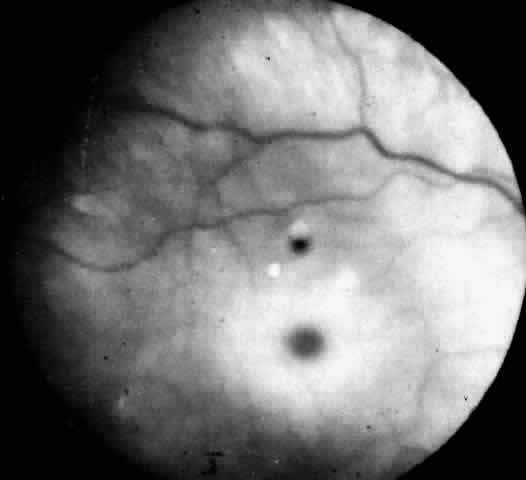

Recognition of the cherry-red spot at the macula is a major diagnostic criterion of Tay-Sachs disease (Fig. 3). It is caused by the accumulation of intracytoplasmic membranous bodies in retinal ganglion cells.

Fig. 3. Fundus of an 18-month-old boy with Tay-Sachs disease. Note cherry-red spot and small white parafoveal halo.

The circular appearance of the fundoscopic lesion reflects the anatomy of the macula. No ganglion cells are present at the very center of the macular region, the foveola, and the central red spot simply represents the normal choroidal background color. The ganglion cell layer surrounding the foveola is several cells thick, and loading of these neurons by storage products results in loss of retinal transparency and a white parafoveal halo. Peripheral to the macular region the ganglion cell layer is only one cell thick, and lipid accumulation in these cells is, therefore, less conspicuous.

Tay-Sachs disease is also the most common storage disease causing macular cherry-red spots (Table 2).3 The variation in the shade of the red spot reflects racial fundus pigmentation. The halo is opaque, slightly elevated, and 1.5 disc diameters in width. The outer border is less sharp than the inner border.

A more widespread opacification of the retina can occur due to involvement of the ganglion cells in the posterior pole. This was observed by Wray4 in a 3½-year-old child with Tay-Sachs disease. The child had black hair and brown eyes, and the cherry-red spot at the macula was brown. The patient was blind, with marked optic atrophy (Fig. 4).

Fig. 4. Fundus of 3 1/2-year-old girl with Tay-Sachs disease. Note cherry-red spot, an extensive white parafoveal halo, and optic atrophy.

A dynamic process of development of the macular cherry-red spot occurs paralleling the infant's progressive neurologic disorder. The cherry-red spot can be observed as early as 2 months of age and is conspicuous at age 4 to 6 months. Loss of visual acuity may occur without noticeable change in the circular halo. But, in time, the ganglion cells atrophy and optic atrophy and loss of the nerve fiber layer occurs. At this stage blindness coincides.